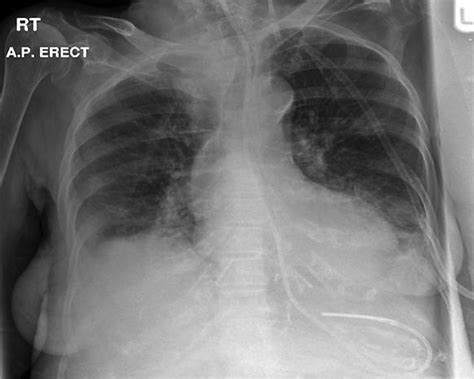

Complications of Ng Tube Insertion

While Ng tube insertion is generally safe, it can be associated with several complications:

• Nasal Trauma: Insertion can cause nasal bleeding or ulceration.

• Esophageal Perforation: Although rare, the tube can perforate the esophagus, leading to serious complications.

• Aspiration: There is a risk of aspirating stomach contents into the lungs, which can cause pneumonia.

• Tube Dislodgement: The tube can become dislodged, requiring reinsertion.

• Patient Discomfort: The procedure can be uncomfortable or painful for the patient.